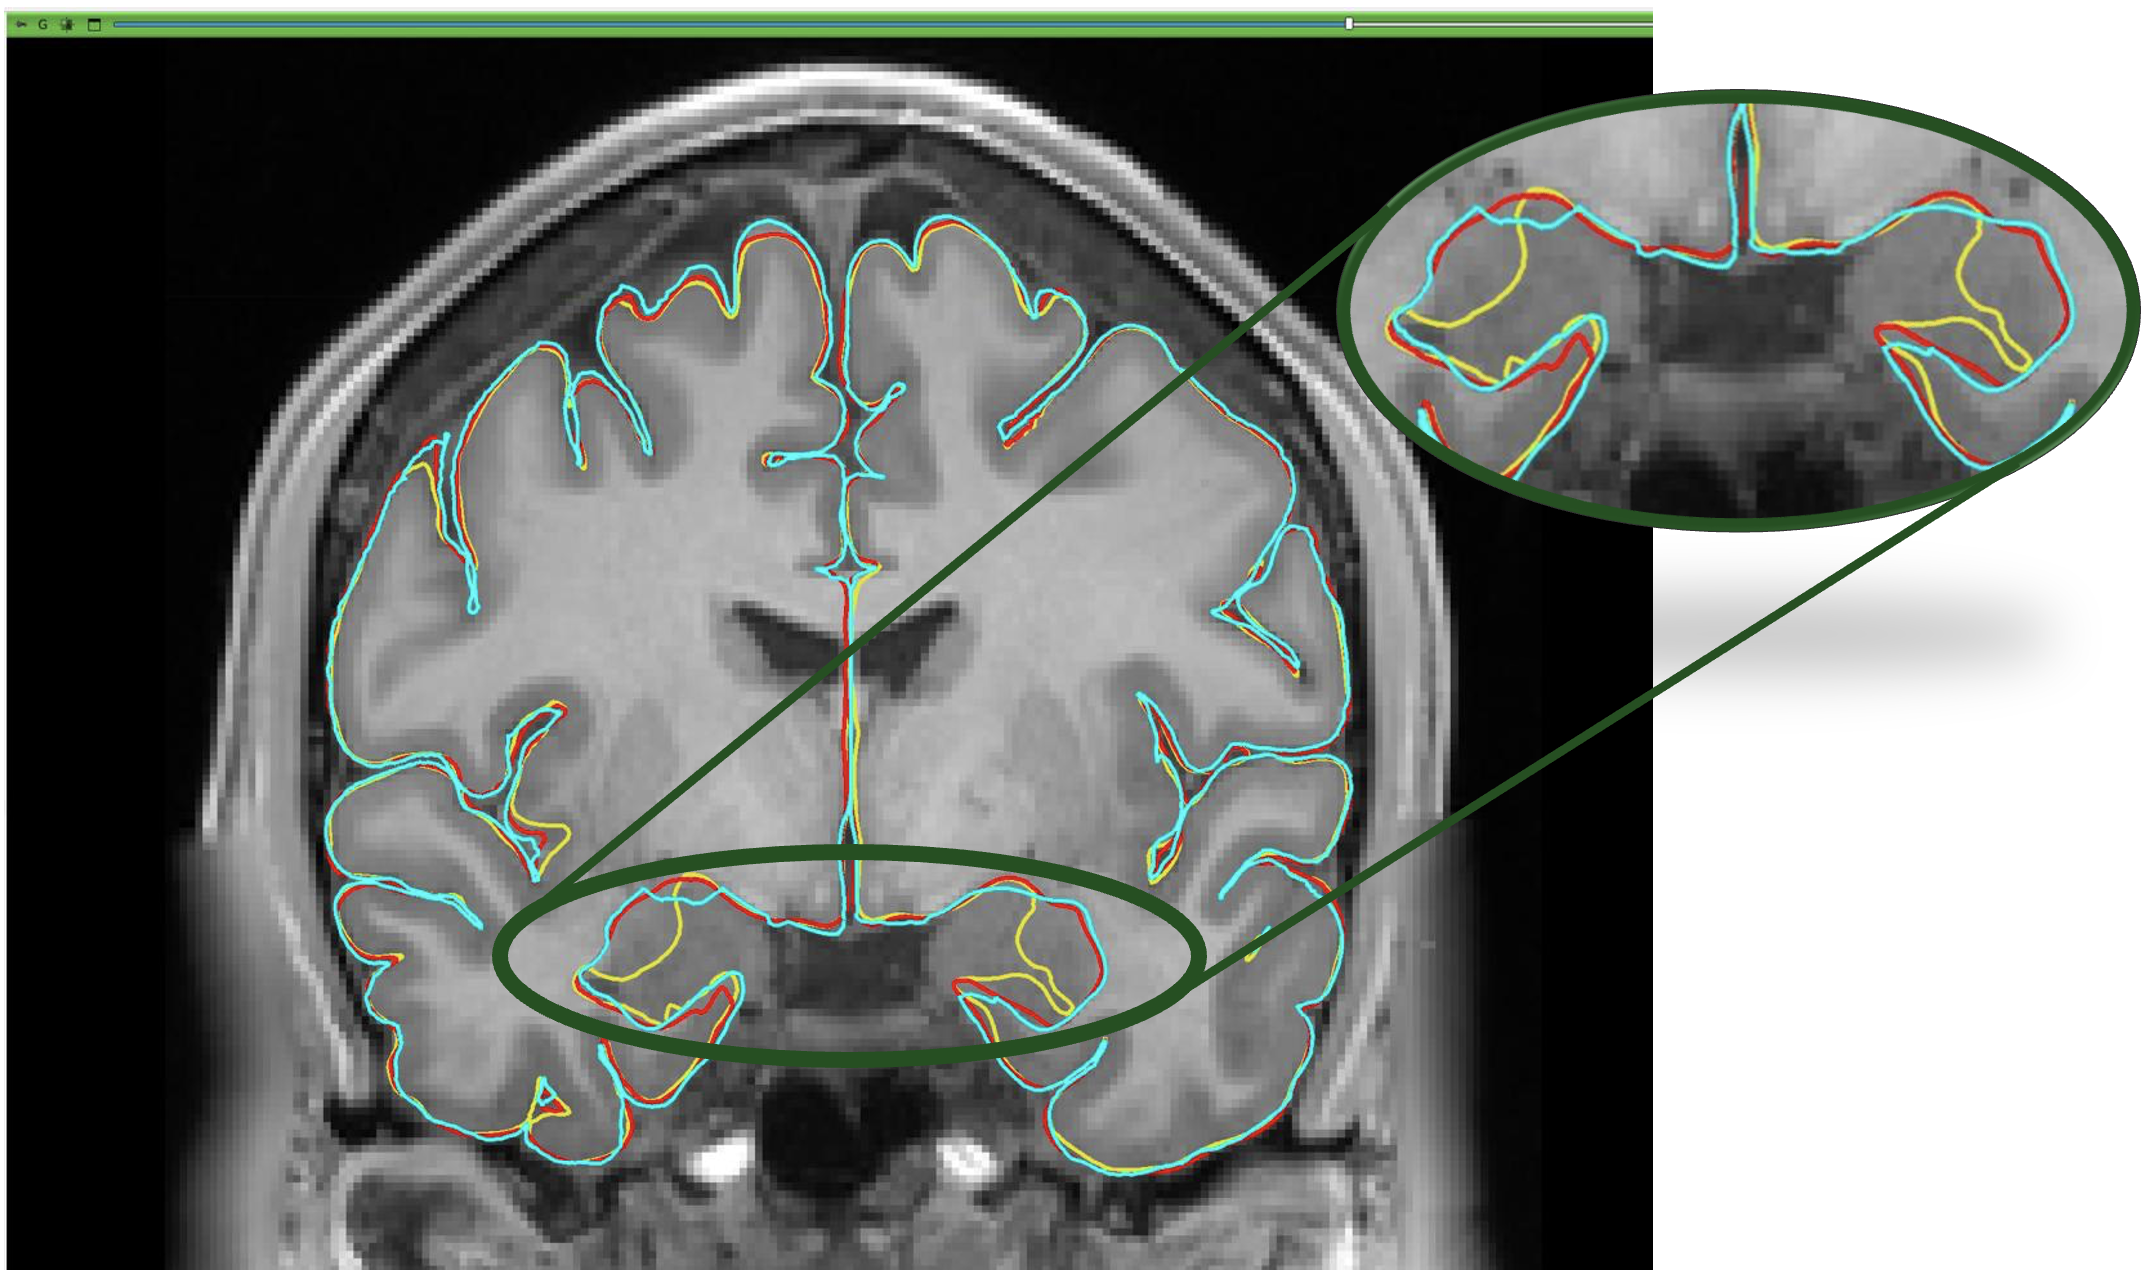

This Figure illustrates the differences between ground truth and predictions.